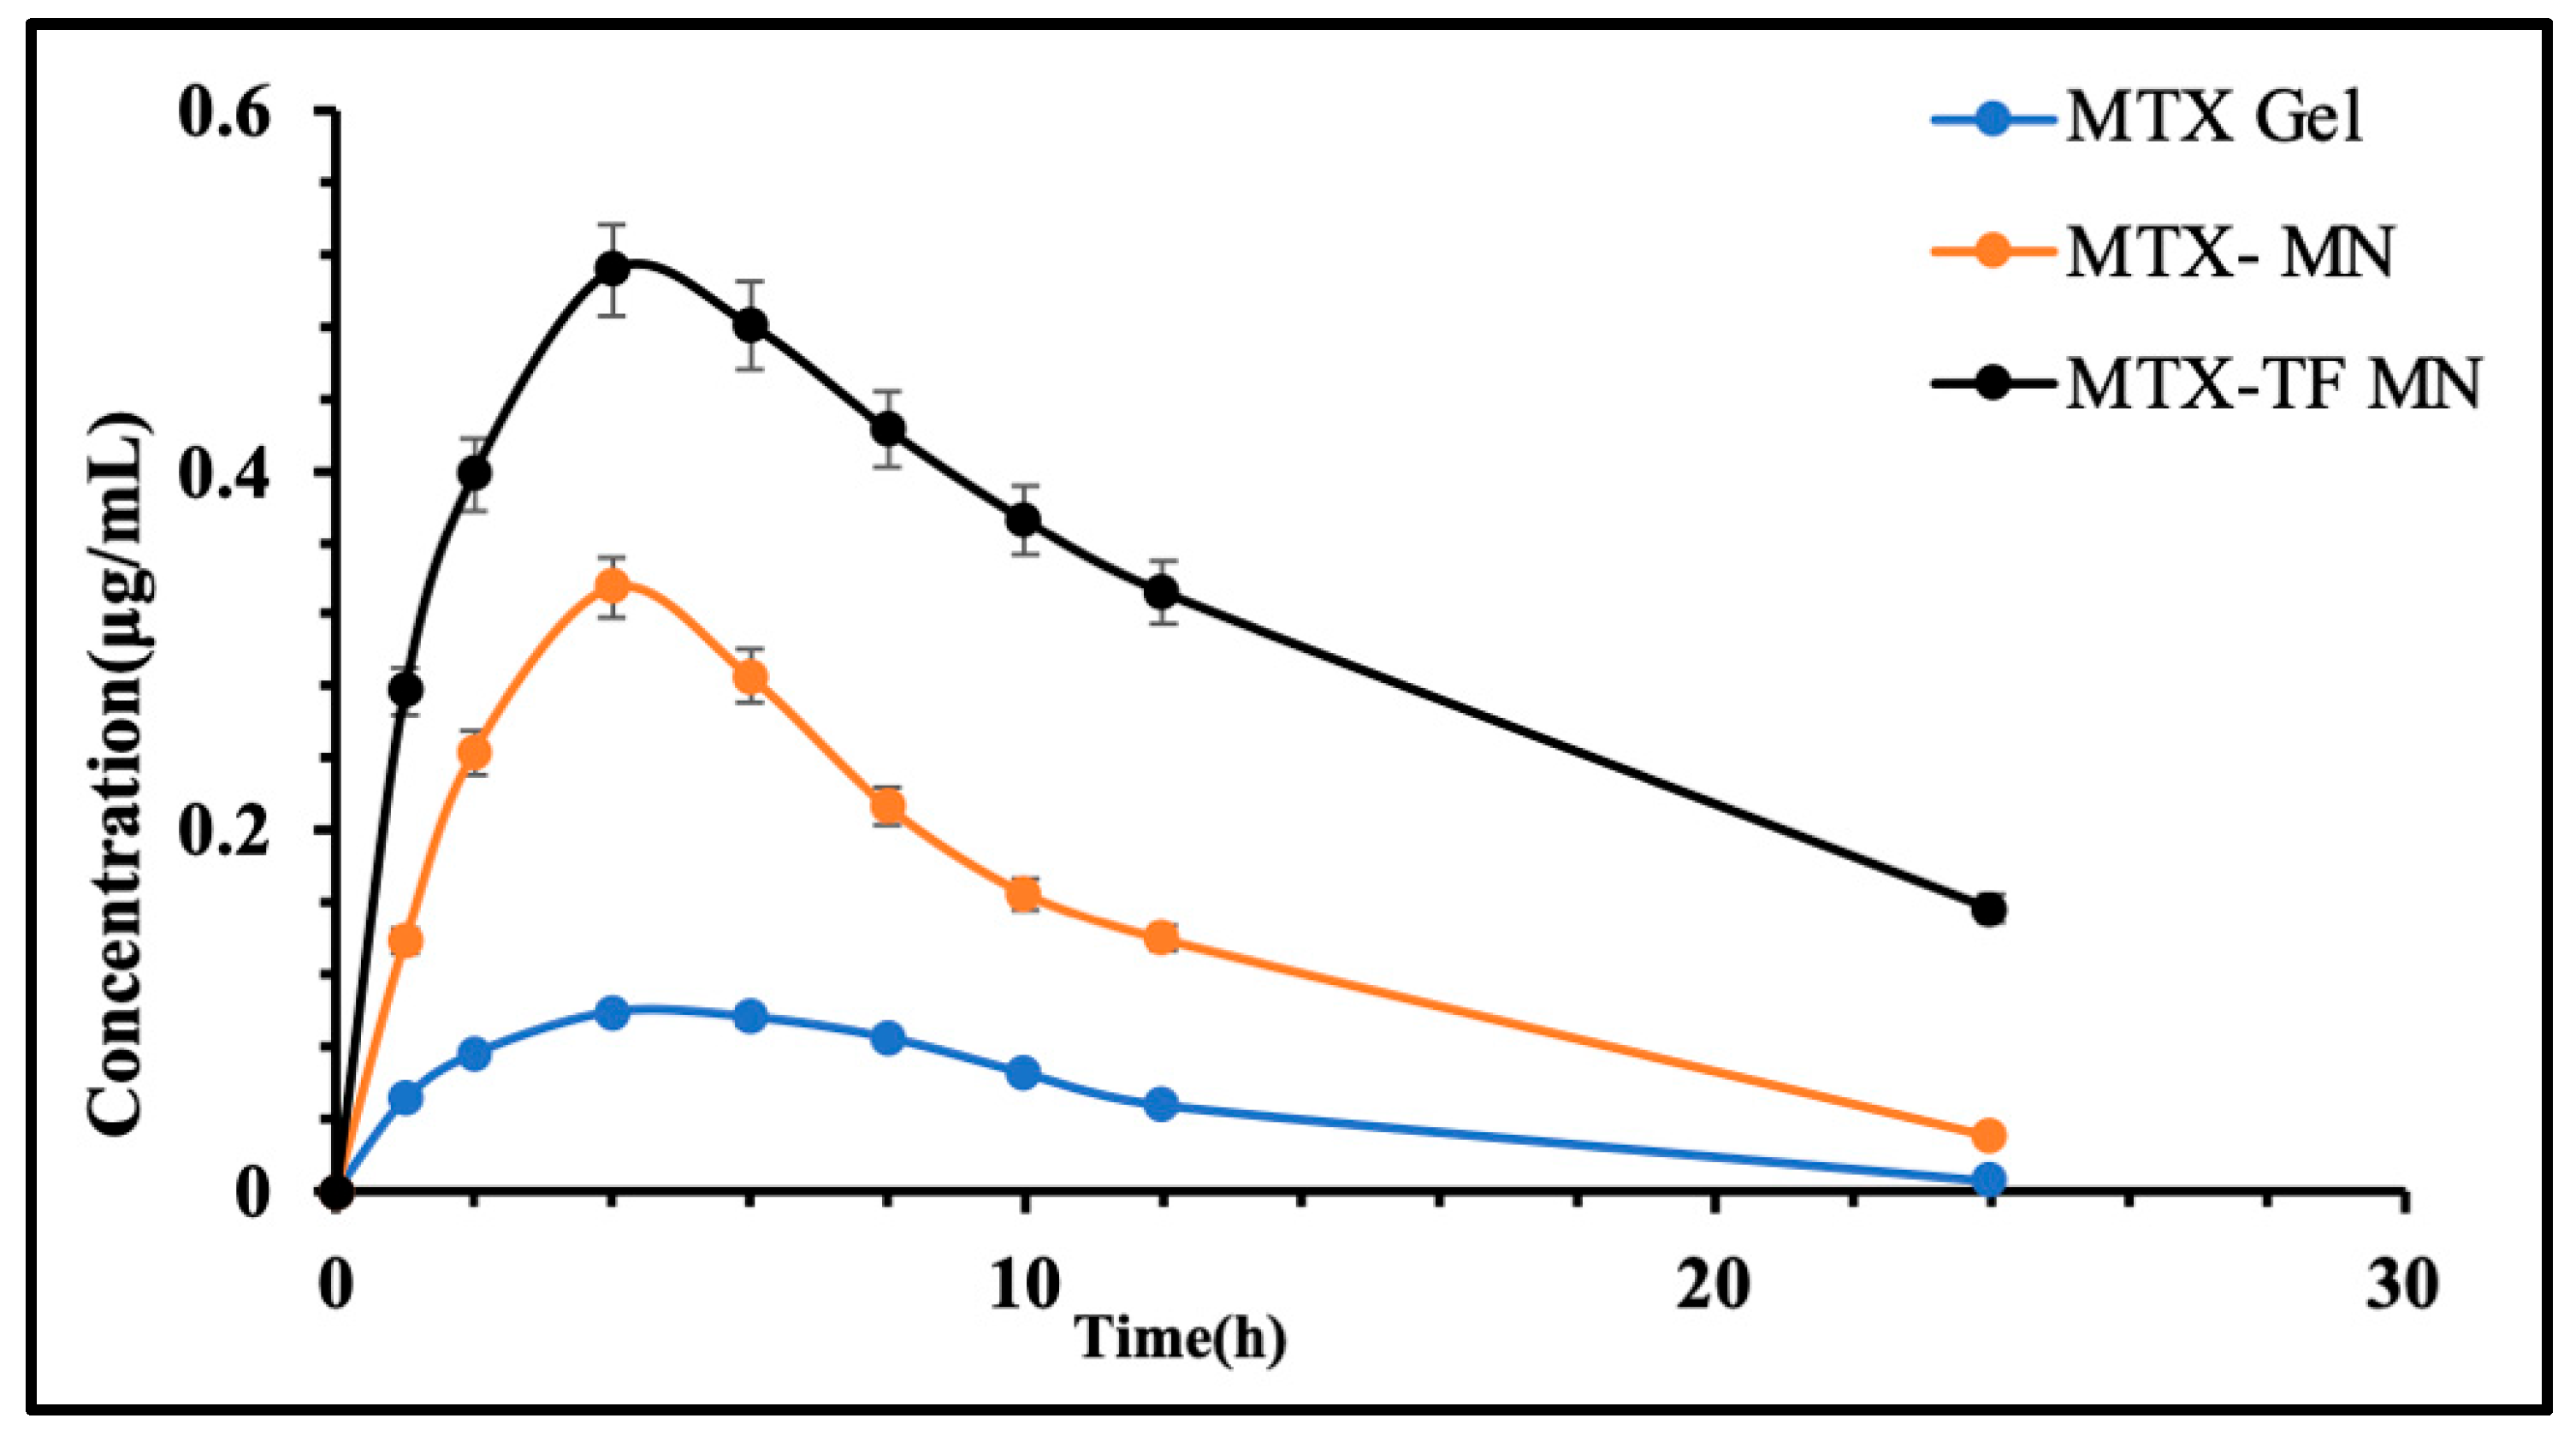

2.6.5. In Vivo Pharmacokinetic Assessment

3.4.5. In Vivo Pharmacokinetic Assessment

| Parameters | Plasma | ||

|---|---|---|---|

| MTX Marketed Gel | MTX-MN | MTX-TF-MN | |

| Tmax (h) | 2.5 ± 0.0 | 3.1 ± 0.15 | 3.4 ± 0.17 |

| Cmax (μg/mL) | 0.25 ± 0.16 | 0.47 ± 0.27 | 0.50 ± 0.41 |

| AUC0–t (μg/mL·h) | 2.25 ± 0.51 | 4.94 ± 0.27 | 7.68 ± 0.24 |

| AUC0–∞ (μg/mL·h) | 2.27 ± 0.17 | 5.15 ± 0.21 | 10.26 ± 0.11 |